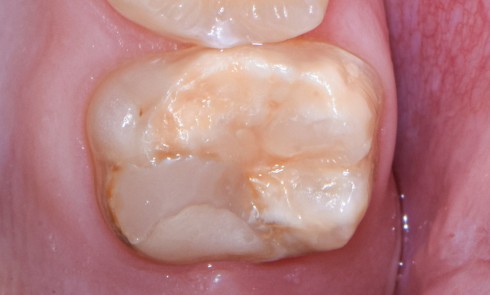

Article réservé à nos abonnés Le scellement dentinaire immédiat

Scellement dentinaire immédiat : concept Historique Les protocoles de mise en œuvre des restaurations indirectes nécessitent classiquement (hors CFAO directe...